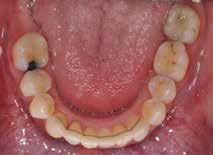

INTRODUKTION OG FORMÅL – Ortodontisk behandling kan være en nødvendighed hos patienter med avanceret parodontitis (stadie 3 og 4), hvis der skal genetableres funktionel okklusion, tilfredsstillende æstetik samt være mulighed for indsættelse af tanderstatninger. Formålet med denne artikel er at præsentere kliniske retningslinjer og en behandlingsmodel for ortodontisk behandling af patienter med velbehandlet parodontitis.

MATERIALE OG METODER – Artiklen bygger på en gennemgang af internationale retningslinjer og kliniske erfaringer, herunder to patienttilfælde, hvor der er foretaget ortodontisk behandling af patienter med stadie 3- og 4-parodontitis. Der beskrives rammer for en systematisk tilgang med fokus på parodontal sundhed, ortodontisk korrektion og livslang vedligeholdelse, hvor hele behandlingen udføres i et tæt interdisciplinært samarbejde.

RESULTATER – Begge patienter opnåede sunde parodontale forhold, funktionel okklusion og forbedret æstetik. Ortodontisk behandling blev iværksat efter opnåelse af parodontal stabilitet og tilpasset det reducerede parodontium med kontrollerede kraftsystemer. Under behandlingen blev parodontiet vedligeholdt, og efter afsluttet ortodontisk behandling blev patienterne fulgt med regelmæssige kontroller af både parodontal sundhed og ortodontisk retention.

KONKLUSION – Ortodontisk behandling af patienter med velbehandlet parodontitis er mulig og kan give gode æstetiske og funktionelle langsigtede resultater med en interdisciplinær tilgang og efterfølgende fokus på vedligeholdelse og retention.

PARODONTITIS kan ubehandlet resultere i ændringer i tandstilling og belastningsforhold, hvilket ofte medfører et behov for ortodontisk behandling. Fra patientens perspektiv vil ønsket om ortodontisk korrektion ofte bero på et ønske om forbedret æstetik (1), mens det fra et tandlægefagligt synspunkt også er muligheden for at opnå en hensigtsmæssig okklusion med bedst mulig kontrol over belastningsforhold, der fører til anbefaling af ortodontisk behandling. Formålet med denne artikel er at præsentere kliniske retningslinjer, der på forsvarlig vis sikrer ortodontisk behandling af patienter med velbehandlet parodontitis.

Vi viser her to ortodontiske behandlinger af patienter med velbehandlet stadie 3- og 4-parodontitis, som begge har tandtab og reduceret, men sundt parodontium, dog med begrundet undtagelse af en enkelt tand, som vi kommer tilbage til. Behandlingerne følger følgende princip:

PATIENTTILFÆLDE 1

Patienttilfælde 1 (Fig. 1) er en 37-årig kvinde, henvist efter succesfuld behandling af stadie 3-parodontitis. Der er nu sundt

Før behandling

parodontium, ingen pocher over 4 mm, og både blødnings- og plakindeks er under 10 %. Patienten er motiveret for ortodontisk behandling, da hendes tænder er vandret over tid, delvist som følge af reduceret parodontium.

Der ses anterior trangstilling i begge kæber og overerupterede 1+1 og 2,1-1,2, hvilket resulterer i dybt bid med 2- tæt på ganepåbidning. Der er normale sidetandsrelationer, men der ses 5 mm horisontalt overbid (HOB) og 7 mm vertikalt

overbid (VOB). Papillen mellem 1+1 er betydeligt reduceret pga. fæstetab, og de mesialt kippede 1+1 har resulteret i en ”dark triangle”. Den facioorale funktion er for nuværende i.a. Panoramarøntgen (Fig. 1, I) viser marginalt knogletab i begge kæber og fravær af 8,7+7,8 og 8,7-8.

Objektivt anbefales behandling af det dybe bid, som ubehandlet forventes at forværres yderligere over tid. Patienten har ønske om behandling med æstetisk ortodontisk apparatur, alignere, og det vurderes muligt at behandle malokklusionen med alignere. Dog anbefales det generelt, at alignere undgås eller benyttes med væsentlige modifikationer af alignerens retention ved tandmobilitet, da dette ellers kan medføre jiggling, når aligneren tages af og på mange gange dagligt. På den anden side er der nogen evidens for, at alignerbehandling er associeret med bedre renhold og parodontal sundhed sammenlignet med fast apparatur (16).

Ortodontisk behandling af patienter med parodontitis kan ofte foretages sikkert ved at følge en systematisk tilgang, der omfatter 1) inflammationskontrol, 2) ortodontisk korrektion og 3) livslang vedligeholdelse. Inden behandlingen påbegyndes, skal parodontiet generelt være sundt med pocher på maksimalt 4 mm og et plak- og blødningsindeks under 10 %. Restfæstet skal være tilstrækkeligt til at modstå behandlingen, som udføres med kontrollerede kraftsystemer. Målet er at forbedre æstetik og opnå normal funktion, som kan vedligeholdes på lang sigt samt facilitere restaurerende behandling.

Der planlægges alignerbehandling af begge kæber med intrusion af 1+1 og 2,1-1,2, nivellering af trangstilling UK med interproksimal reduktion (IPR) (Fig. 2 A, B) og senere IPR OK for reduktion af dark triangles mellem incisiverne efter nivellering. Patienten instrueres i at benytte alignere 20-22 timer/ dag med alignerskift hver 7. dag, og patienten ses hver 3.-8. uge under forløbet. Den første alignerserie består af 16 alignere for nivellering OK/UK og IPR i UK (Fig. 2). Efter denne serie planlægges IPR mellem incisiverne i OK for reduktion af dark triangles (Fig. 3) samt yderligere intrusion af OK og UK-fronten i 12 refinement-alignere. Patienten udviser god kooperation og er meget tilfreds med alignerapparaturet, som er mindre synligt end det faste apparatur (Fig. 4).